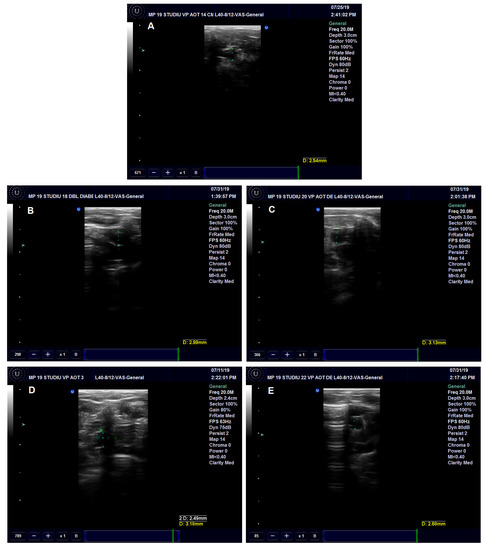

3.3.1. Ultrasound Aorta Examination